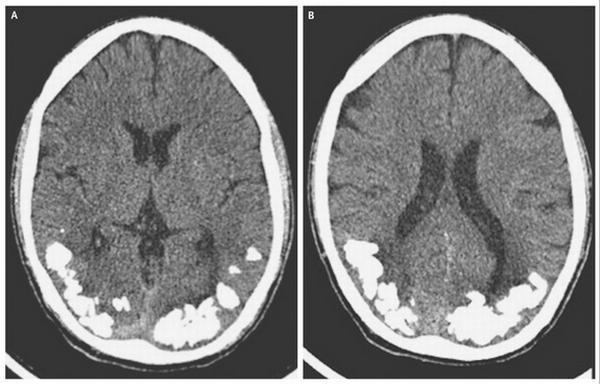

Un homme a découvert que les maux de tête dont il souffrait depuis une dizaine d’années étaient dus à des  cailloux de calcium dans son encéphale.

Il aura fallu 10 ans à ce Brésilien pour connaître la raison de ses violents maux de têtes ainsi que de ses troubles visuels. Après avoir passé un scanner, il a appris que des cailloux de calcium se trouvaient à l’arrière de son cerveau, dans la zone responsable de la vue. Ils étaient le résultat d’une maladie cœliaque ou intolérance au gluten. Des tests ont révélé la présence d’anticorps associés à cette pathologie dans son liquide céphalo-rachidien.

Après le diagnostic, l’homme a entamé un régime sans gluten et la prise de comprimés de fer, ses analyses sanguines ayant révélé une carence. Il s’est également vu prescrire un traitement contre l’épilepsie. Son état s’est alors amélioré. Si les médecins de l’université de São Paulo qui l’ont traité ne peuvent expliquer avec certitude cette accumulation de calcium dans le cerveau, ils supposent que l’incapacité à absorber le fer peut en  être à l’origine.